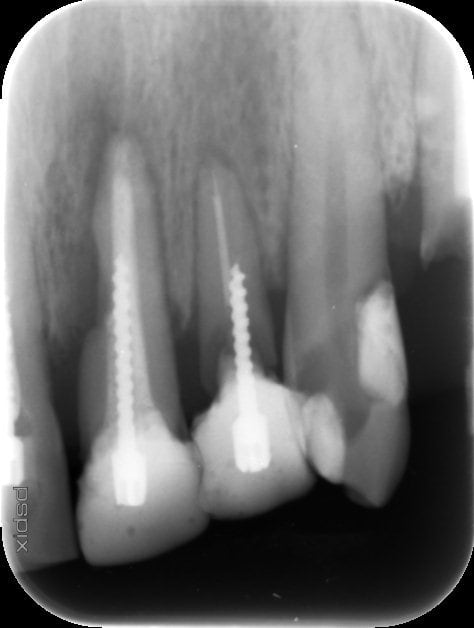

Bonsoir à tous, cette 21 doit etre intégrée à un bridge mais l'image sur la racine en mesial m'inquiète.

S'agit il d'une rhyzalyse interne ; cette dent a subi un traumatisme important il y a 20 ans avec une luxation de la dent qui a été remise dans son alvéole

Cette dent est silencieuse pas de douleur mais une légère mobilité.

Non la question était: peut ton raisonnablement intégré la 21 a un bridge (l'étendue du bridge n'étant pas précisé)? pour répondre à cette question je pense que la radio est plus que suffisante. La valeur de cette dent comme pilier pour un bridge est très mauvaise. Résorption externe semblant aller presque jusqu'au canal, suspicion d'infection peri-apical, reprise d'endo probablement impossible ne serai ce qu'a cause du screw post indémontable sans risquer la fracture ou l'avulsion. Pas besoin de connaitre la configuration du bridge, l'état des autres pilier, l'occlusion ou autre paramètre pour juger de la valeur de la 21 dans ce cas.

21 (perforée par le SP), 22 (super cariée, rapport C/R défavorable) et peut-être bien 24 sont mortes, tu vas au devant des problèmes si tu cherches à conserver ça.

c'est clair, la 21 a une résorption externe, donc dent pas fiable, direction le bassinet...

au vue de ta radio, la 22 a une reprise de carie très importante, tout comme la 24, la 23 elle, semble conservable

si je t'interroge sur l'état buccal de ta patiente, c'est tout simplement que, admettons que tu puisses sauver la 22 et la 24, les piliers deviendront quand même extrêmement fragiles et là l'occulsion deviendra fondamentale si tu veux pas avoir ta patiente tous les 4 matins sur ton fauteuil pour re-sceller le bazar et conduire là où on sait...(fracture, extrac, etc...)